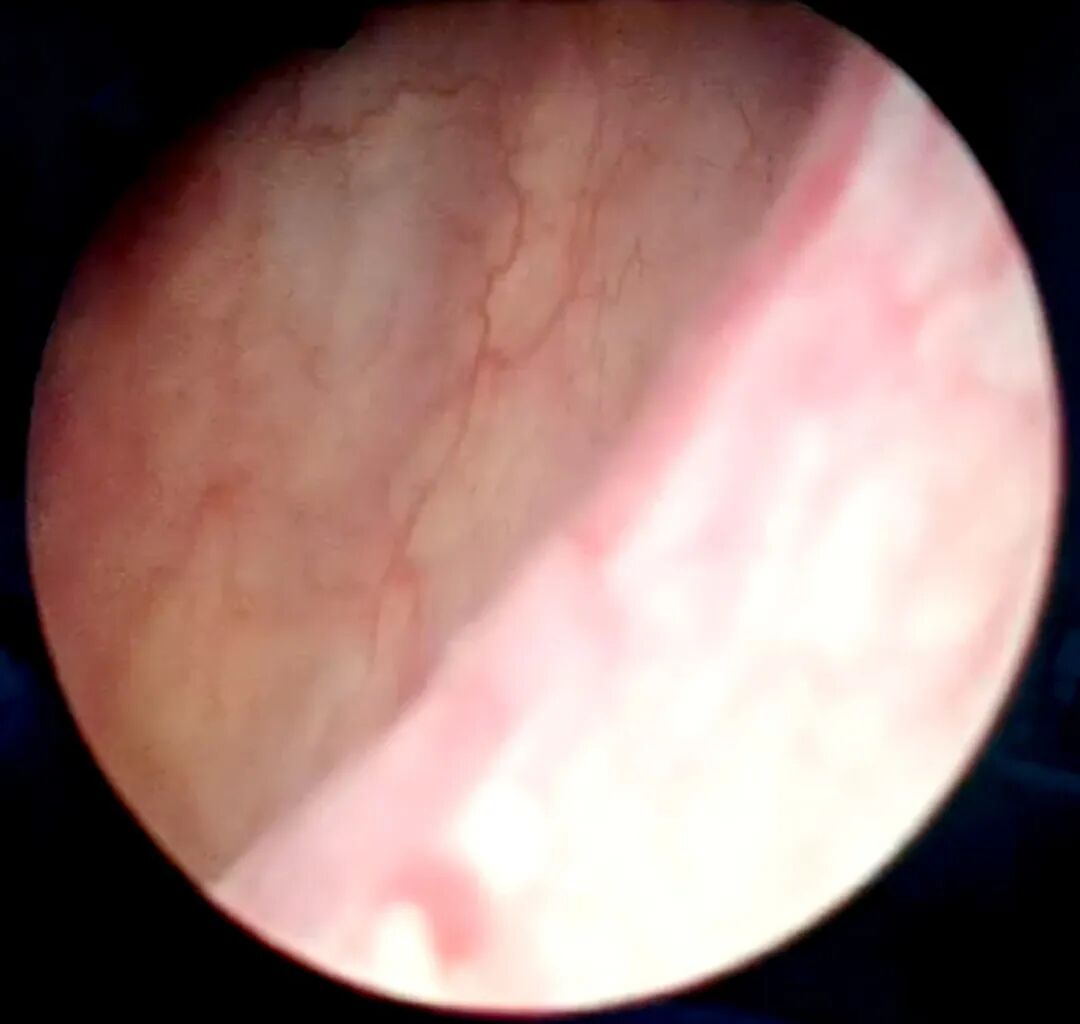

对于这样的结果,曾先生感到惊喜又不可思议。随后团队为其进行了膀胱镜复查,检查发现膀胱粘膜光滑且看不见肿瘤;随机电切取出的标本被送往病理科进行分析,分析结果也再次证明,肿瘤完全“消失”了。

▲膀胱镜下可见,膀胱粘膜光滑看不见一点肿瘤